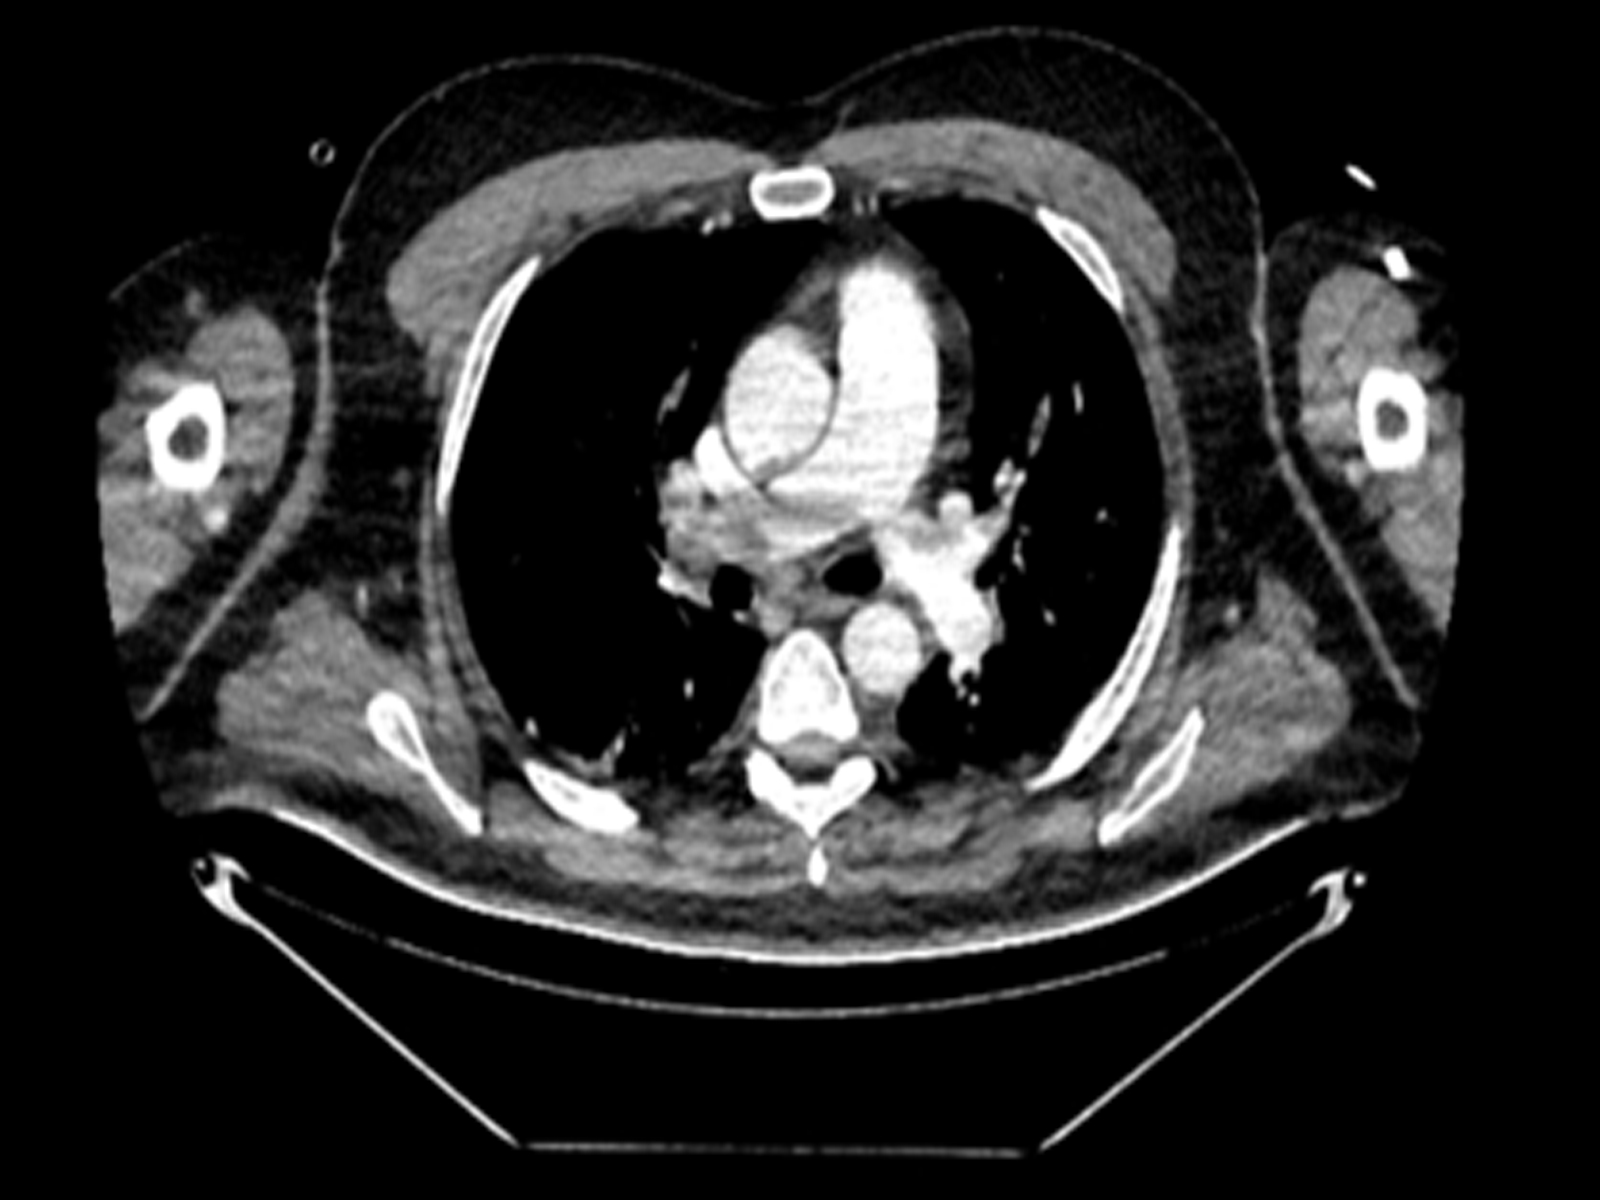

Ultrasound Facilitated Catheter Directed Thrombolysis in the Treatment of Acute Pulmonary Embolism: A Case Series of Six Patients

Pervin Hancı, Başak Gönen, Osman Kula, Gökhan Karataş, Ethem Yıldız, İlker Yılmam, Osman Nuri Hatipoğlu doi: 10.5505/respircase.2026.84758 Pages 14 - 21 |